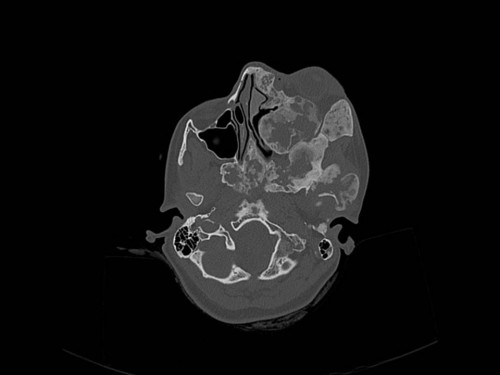

Eine 16-jährige Patientin kommt in eine MKG-chirurgische Praxis zur Abklärung der weiteren Vorgehensweise bzgl. ihrer Erkrankung.

Sie betrachten die angefertigten Röntgenbilder. Welche der folgenden Röntgenbefunde ist korrekt? Ossäre Auftreibungen im Bereich …

- A… der Mandibula links.

- B… des Os frontale links.

- C… des Os zygomaticum links.

- D… des Os temporale links.

- EAlle genannten Aussagen sind korrekt.

Bildgebung - OPAN 2004